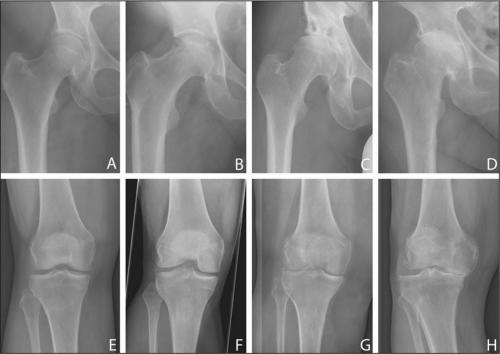

Слева направо — ухудшение состояния суставов по причине заболевания.

Остеоартроз тазобедренного сустава 1 степени, лечение которого будет эффективно медикаментозным путем, не провоцирует острых симптомов; мало кто из пациентов сразу обращается к врачу. Это влечет запускание болезни и переход ее в следующую степень протекания. На снимках рентгена еще не сильно заметны нарушения.

Остеоартроз тазобедренного сустава 2 степени характеризуется выраженным уменьшением пространства в суставной щели. В таком состоянии хрящи уже сильно повреждены, что провоцирует постоянное трение костей при движении и выраженную боль у пациента. Из-за развития отечности сустав теряет свои функции.

Выявить 2-ю степень несложно, так как при первом же рентгеновском снимке врач заметит существенные отклонения. Характерные признаки второй степени заболевания:

Деформирующий остеоартроз левого ТБС. Обратите внимание, как изменились очертания левого суставного сочленения по сравнению с правым.